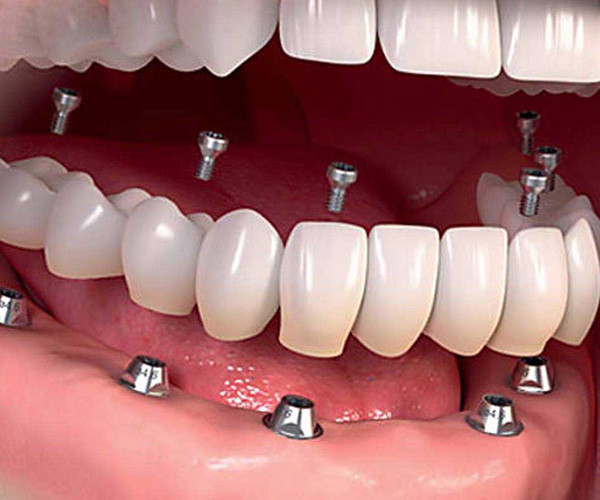

Yes it is possible to get a whole new set of teeth

Struggling with dental issues can be painful and stressful. If you’ve been dealing with tooth loss and wish you could have a new set of teeth, implant surgery can make this happen.

Dental implants have been in use for decades now and have an excellent track record. These teeth act just like your regular teeth so you have no food restrictions and they don’t need a complicated maintenance routine, just good oral hygiene practices and routine check-ups will suffice to keep them in good shape.

Why should I choose implants over dentures?

Dentures are a temporary, removable set of replacement teeth that fit into your jaw. Unfortunately, they have a tendency to move when you’re eating or speaking. This can make it difficult to speak clearly or to enjoy a meal. Dentures also need an intensive care routine to keep them in good shape.

But with dental implants these problems are avoided as your replacement teeth are firmly fixed and immovable. They are more comfortable and behave exactly as your natural teeth would.

Can I have all my teeth pulled and get implants?

Yes, it is possible to get a whole new set of teeth. This is often the route chosen by those who have been dealing with dental distress for years.

Permanent dental implants are made with metals like titanium or zirconia. They are embedded well into the gum line and act just like the roots of your teeth. Replacement teeth are then affixed onto these implants. Dental implants can last a lifetime and are considered to be a permanent solution for tooth loss. All-on-four and all-on-six dental implant surgeries can be done to give you a new set of teeth in just one jaw or your entire mouthful of teeth.

The experienced dentists at Dental Artistry are able to insert implants in your jaw and fix in a whole new set of teeth that are anchored firmly by the implants. Not only are these a permanent, more efficient solution but they also prevent bone loss or erosion and the consequent sagging of the face often associated with dentures.

How many implants are needed for a full mouth?

Dental Artistry offers the option of giving you a full set of teeth with just four sets of implants. This surgical procedure is called all on four. One implant can hold in place multiple teeth. Sometimes your dentist may recommend that you have six implants instead of six, this is called the all on six procedure. Your dentist will advise how many implants are best for your needs.

How much is a full top set of dental implants?

Every mouth is different, and the final costing will depend on the specific procedures that need to be carried out for your teeth. An approximate costing for a full upper set of teeth would fall somewhere between NZ$18,000 and NZ $30,000. Learn more about the cost of dental implants. Dental Artistry offers finance options so you can book a consultation and discuss this.

How much does it cost to replace all your teeth?

The cost of replacing all your teeth is about double the cost of replacing a full set of your upper or lower jaw. While contemplating the financial investment, do take into account that these implants can last a lifetime and provide long-term benefits like preventing bone erosion, removing any diet restrictions (that you would otherwise have due with other forms of teeth replacement) and are easy to care for. Many who undergo this procedure comment on their newly regained confidence as well.